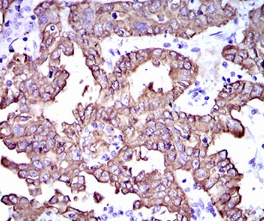

CK5 Mouse Monoclonal antibody[2C2B4]

IHC    1/200 - 1/1000